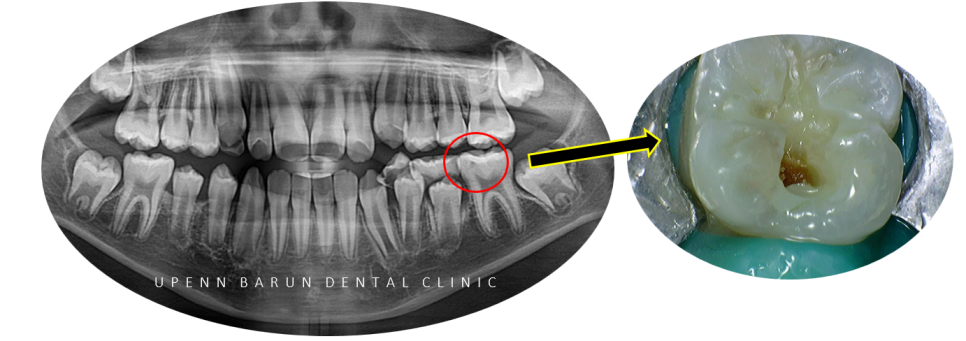

왼쪽 아래(#36) 영구치 충치 엑스레이 및 구내 포토

교정을 시작하기에 앞서

엑스레이를 확인해 보니 충치가 생겨

충치치료를 마무리하고 교정을 진행해드렸습니다 :)

충치를 제거해보니 생각보다 범위가 컸지만

보존적인 치료를 추구하는 유펜바른치과에서

레진치료로 마무리 해드렸습니다 :)